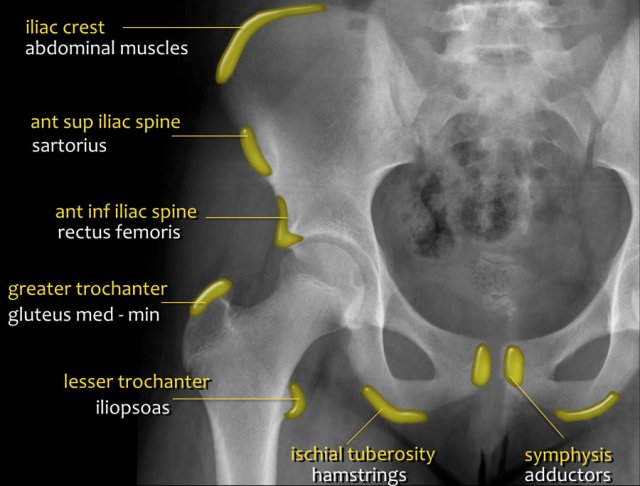

Avulsion injuries of the pelvis are a frequent cause of hip pain in adolescents involved in sports.

Because at this age the tendons are generally stronger than the apophyses, strong muscle contraction can result in apophyseal avulsion fractures.

Avulsion injuries can be acute or chronic.

Typical avulsion injury of the anterior inferior iliac spine at the insertion of the rectus femoris tendon.

Typical avulsion injury of the right ischial aphophysis.